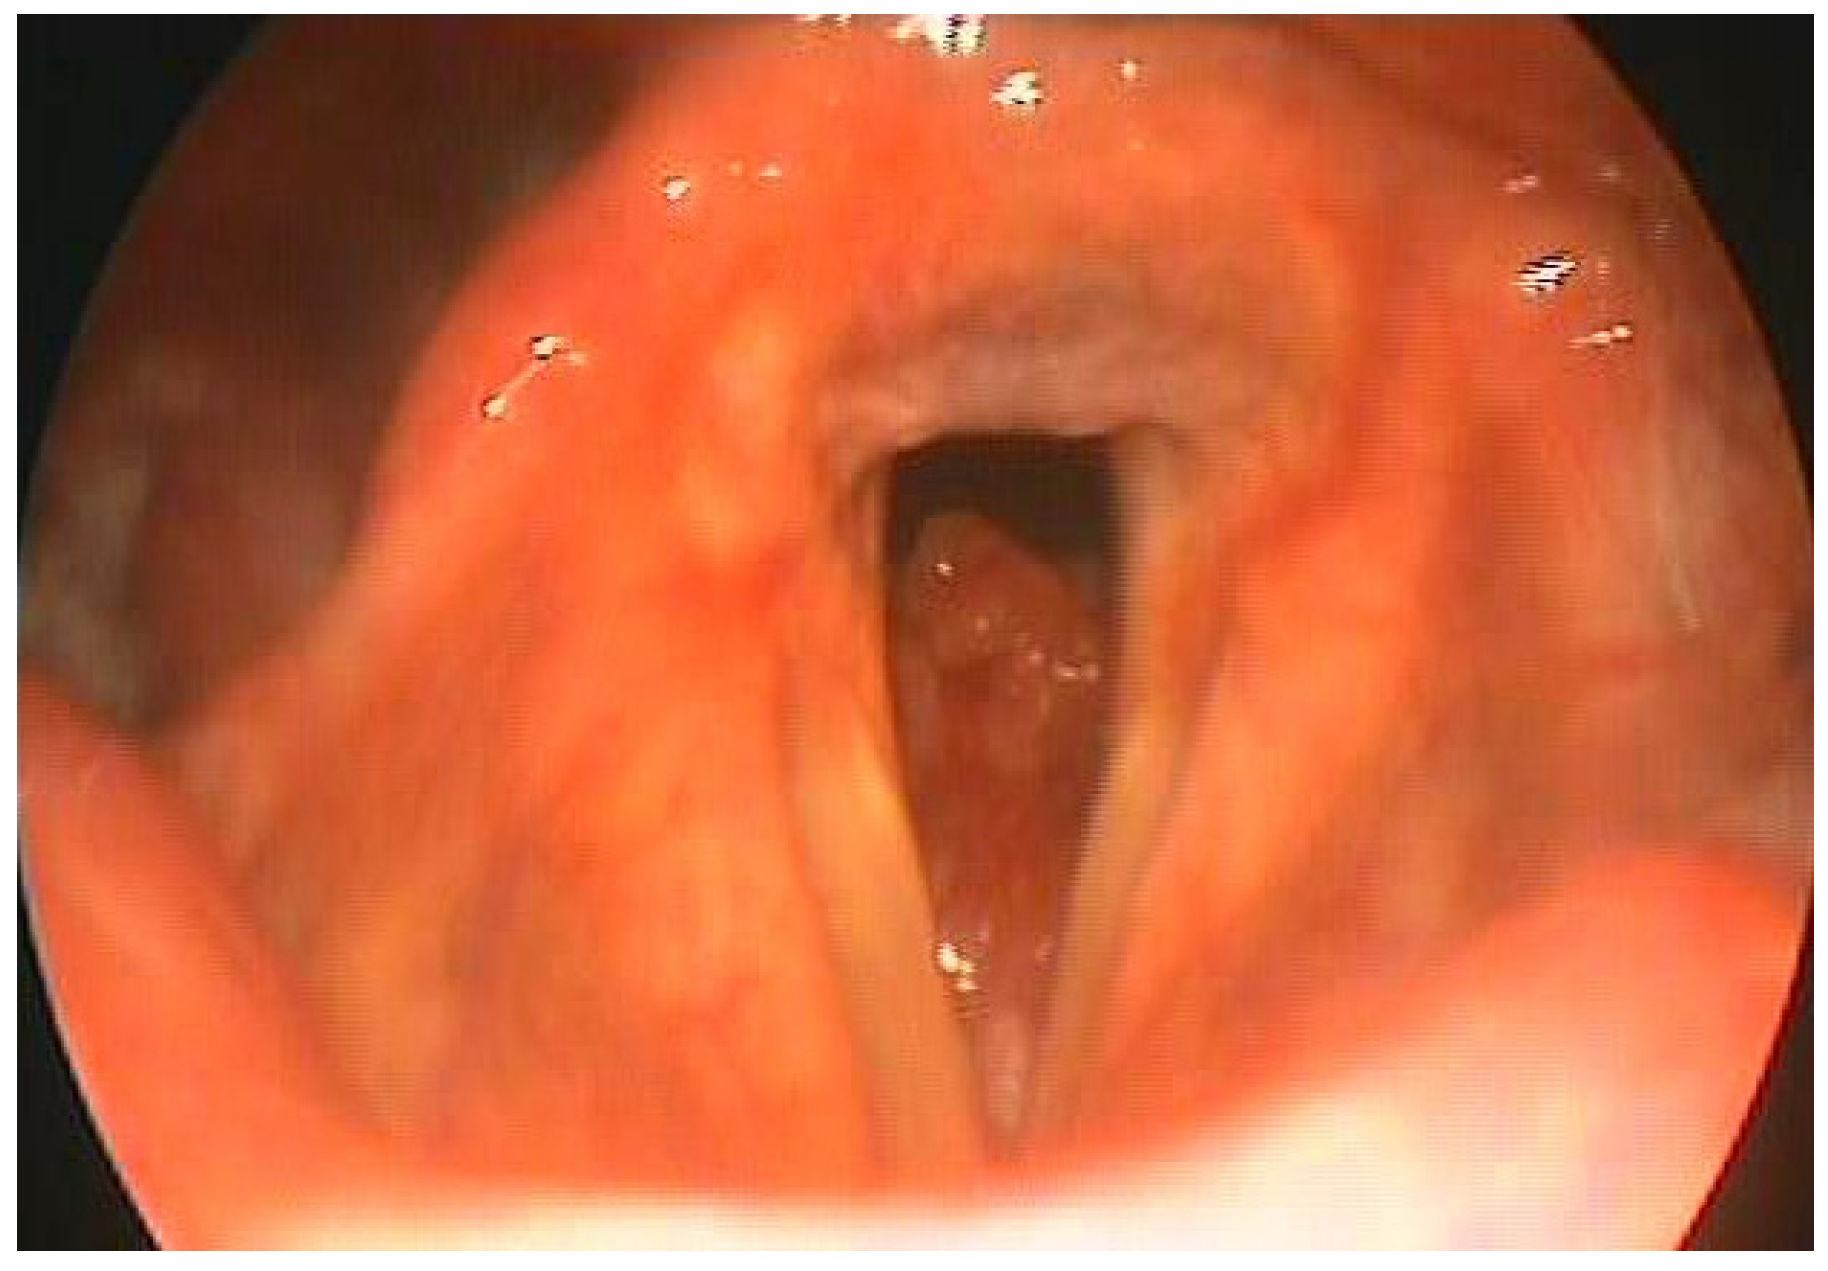

DG aged 60, underwent total laryngectomy and bilateral lateral cervical emptying for adenoid cystic carcinoma which had subglottic localization (Figure 1). The patient was an assiduous swimmer, enrolled in an amateur sports club, had achieved good results in numerous category competitions Seniors. After the operation, the patient experienced an initial period of depression despite the psychological support of our health facility and family members. After having overcome the distrust towards the resumption of sporting activity due to fears about its feasibility, he accepted the invitation to resume the sporting activity. A special device was therefore used (Figure 2). It establishes a watertight seal with a double-cuffed rigid tracheostomy tube. The configuration is similar to a snorkel device. The cuffed tracheostomy tube connects to a flexible hose with an attached mouthpiece. The mouthpiece is gripped with the teeth and sealed by the lips. Air flows through the nose, around the palate, into the mouth, through the Larkel tubing and into the lungs.

Figure 1. Endoscopic view.